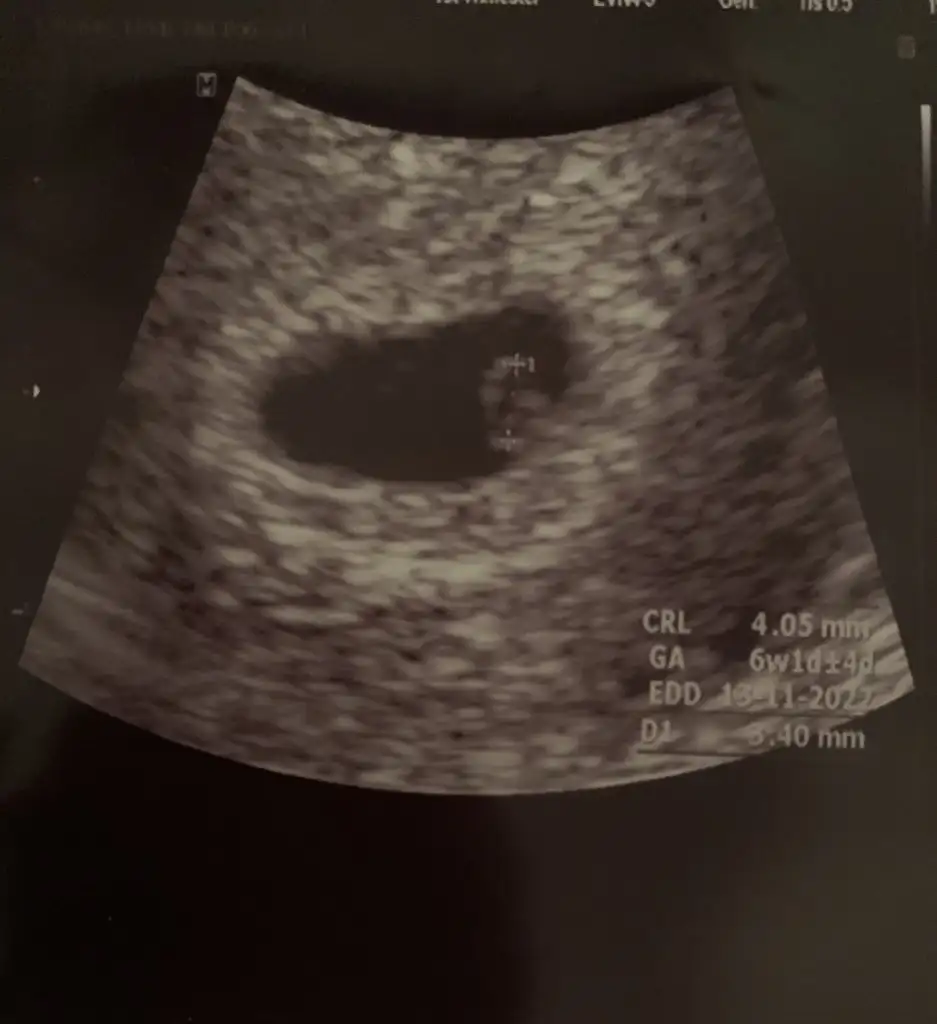

Eveeet geldim, çok şükür kesemizi, bebeğimizi ve kalp atışını gördük🧿 Tek bebek, ikiz değil😁 6+1 SATımla uyumlu hesaplamayı sata göre yapıcaz dedi. Kese çok güzel ve düzgün kenarlarında pütür yok, içinde yolk saç ve bebek de oluşmuş dedi. Kalp atışlarını dinletemem çok duyulmaz dedi ama 2 sn denedi. Bu arada muayenem vajinal oldu, kesinlikle korkmamamı her zaman vajinalin çok daha net olduğunu ve 10. haftaya kadar her türlü şeyi daha net görebileceği için vajinal tercih edeceğini söyledi☹️ Kafamdaki tüm soruları sordum, yürüyüşten kozmetiğe valla kuş gibi hafifledim

Bu da kesemiz ve içinde minnoşumun ilk hali🧿